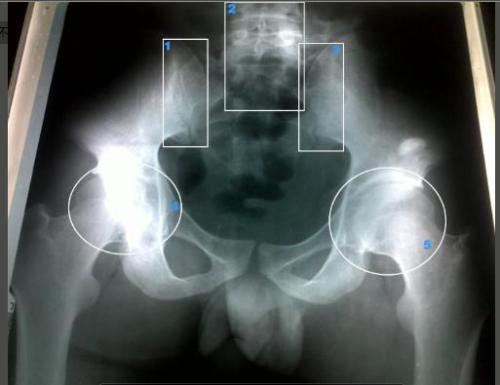

强直性脊柱炎属风湿病范畴、血清阴性脊柱关节病的一种。该病因尚 ...